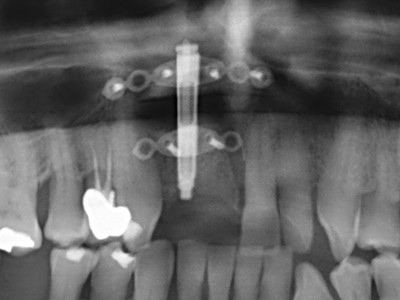

En la extracción de bloques óseos la piezocirugía también presenta ventajas adicionales: Además de la alta precisión en la osteotomía que ya se ha descrito antes, se ha comprobado que el uso de los delgados insertos de sierra resulta especialmente cuidadosas con el hueso. Frente a esto, sobre todo cuando se usan las fresas de Lindemann, cabe esperar pérdidas en la extracción significativamente más altas debido al mayor grosor de la parte frontal del cabezal (Lakshmiganthan, Gokulanathan et al. 2012). La separación basal que se necesita en particular en los injertos de bloque extraídos de forma retromolar se ve facilitada mediante sierras perpendiculares especialmente previstas a tal fin, lo que permite considerar que la cirugía piezoeléctrica es un procedimiento preciso y seguro para la obtención de bloques de hueso en el área retromolar (Happe 2007) (fig. 1-12).

Como ya se ha demostrado en el pasado, básicamente cualquier procedimiento de cirugía de hueso representa una posible indicación para la cirugía piezoeléctrica. Así, la preparación del segmento móvil en la osteogénesis de distracción (fig. 23-25) y en la osteotomía de sándwich puede realizarse con piezas especiales, sin poner en peligro el suministro sanguíneo de la parte crestal, que resulta esencial para el éxito de ambas técnicas (González-García, Diniz-Freitas et al. 2008).

En la cirugía del seno maxilar surgen otros campos de aplicación: En este punto, tras la preparación concéntrica de una tapa ósea de la pared del seno maxilar (que suele tener forma trapezoidal), es posible eliminar patologías y cuerpos extraños del seno maxilar. La tapa ósea se repone después de finalizar la parte intra-antral de la operación y se asegura frente a una posible dislocación mediante cuñas o suturas adaptables.